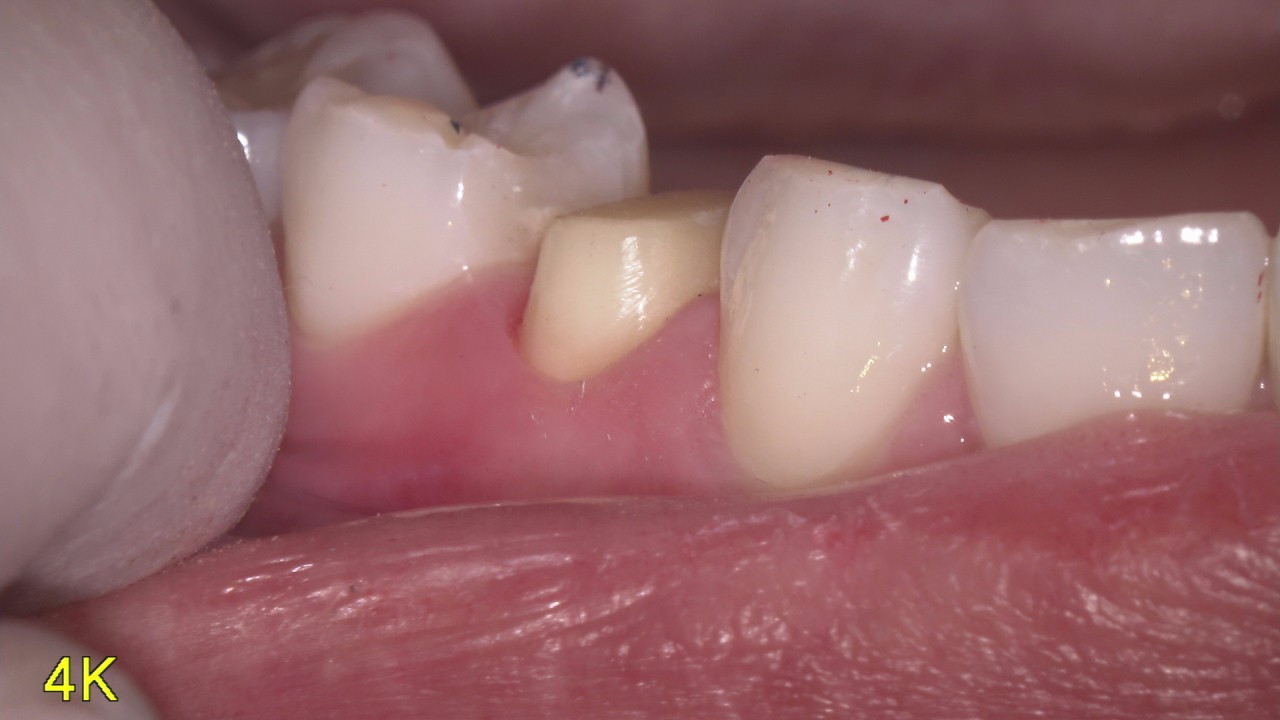

マイクロスコープを使用して口腔内を説明

虫歯って患者さん本人には見えない位置にあったりしてなかなわかりにくいですよね そのために当院では口腔内カメラを内蔵したマイクロスコープを使用して口腔内を説明しています。 写真を撮ったり、動画を撮ったりいろいろ使えるので重 […]